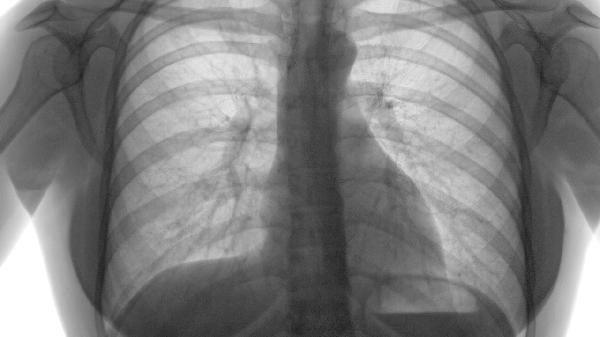

3、桶状胸:

长期肺部过度膨胀会导致胸部前后径变大,形成典型的桶状胸。这是肺组织弹性丧失的一个体征,需要通过肺功能检查来确认。这类情况通常需要长期使用沙美特罗替卡松等复合制剂来延缓病情恶化。